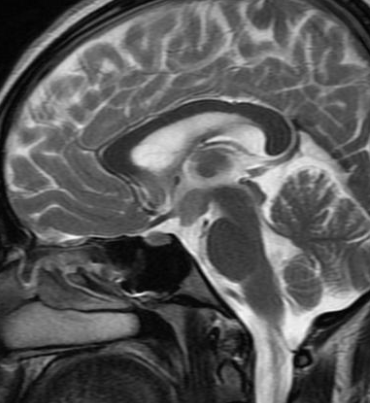

Tuber cinereum hamartoma

IRM

- Masse du tuber cinereum (entre corps mamillaires et tige pituitaire)

- IsoT1, Iso T2

- Pas de prise de contraste Gd+